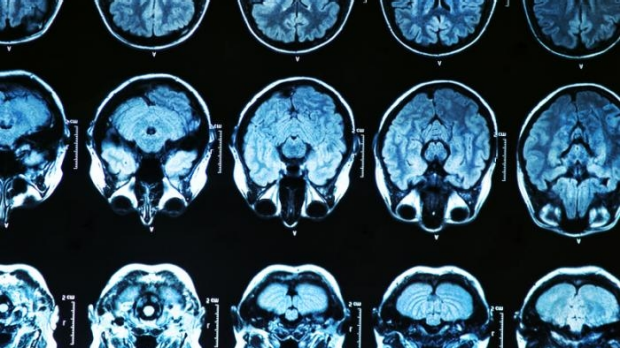

Breakthrough Alzehimer’s drug available to Melbourne patients from next year

A breakthrough Alzehimer’s drug will be available to Melbourne patients from next year, after an early stage trial in the US showed promising results.